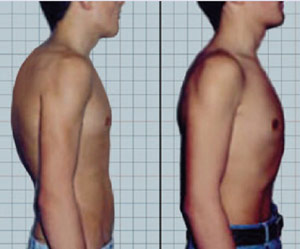

férfi vállát, szenved kyphosis, előretolva kissé döntse le, beesett mellkas területén, gyomor domború.

- Az első fokú - a szög a görbület nem több, mint 30 °. A beteg nincs jelentős panasz az egészségi állapotot. Ha egy férfi nem ruhát, akkor lehet észrevenni enyhe lehajol, kisebb változtatásokat a kések, kis deformáció a vállöv. Sokan nem figyelni az ilyen tünetek a tévhitben, hogy minden rendben van normalizált hamarosan saját.

- Második fokos - szöget görbületi változik 30 ° és 60 °. Egyszerű lomha helyébe külön lekerekített hátsó. Hosszan tartó ülés kellemetlenséget és fájdalmat okoz, mindig van egy vágy, hogy sovány valamit, de ez nem elég az, ami segít. Álló helyzetben C-alakját a hátsó megmarad. Továbbfejlesztése kyphosis provokálja a gerincgörbülés a nyaki és ágyéki gerinc. Dudorok gyomor kiüríti a mellkas.

- A harmadik fokozat - a betegség súlyosabb ívelt szög nagyobb, mint 60 °. Ez jellemzi a kialakulását a púp. Ezzel kapcsolatban egy hajlított hátsó zsugorodik törzs ömlik a mellkas, has dudor határozottan. Oldali tűnik hosszabb. A beteg panaszkodik állandó fáradtság, hátfájás és bordaközi régió légszomj és nem a levegőt. A legfejlettebb formája kyphosis gondjai vannak az emésztőrendszerben, ami kíséri inkontinencia. A immunrendszer legyengül, a test gyengül, ami végül vezethet tartós fogyatékosság.